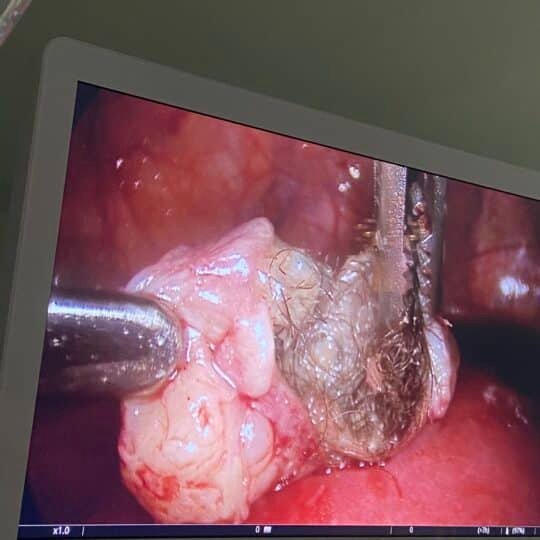

Μαιευτήρας Γυναικολόγος Βόλος Λάρισα | Ρομποτική Χειρουργική Da Vinci X